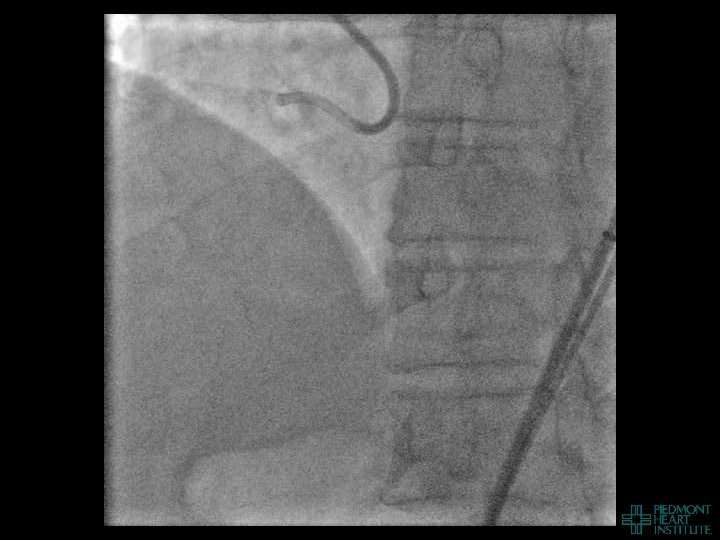

Case Example 4